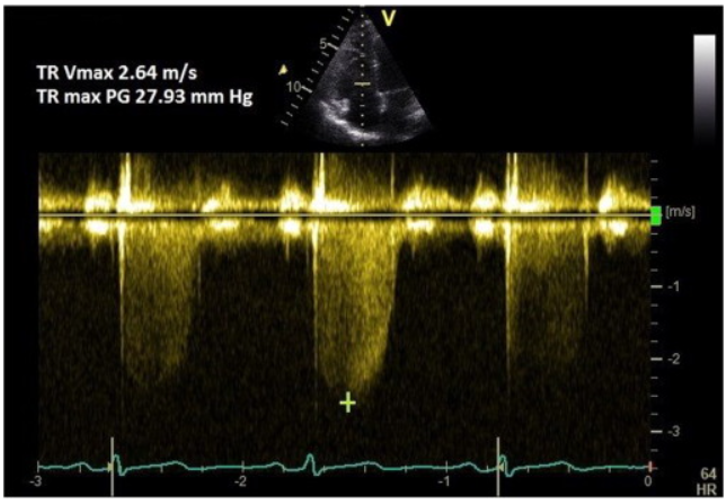

bernoulli equation

∆p = 4v²

pressure gradient across a value is related to velocity

pressure drop across a stenotic valve, in echo, is calculated using this

peak velocity and pressure gradient

caliper to measure PV

PP gradient is calculated based on PV using bernoulli